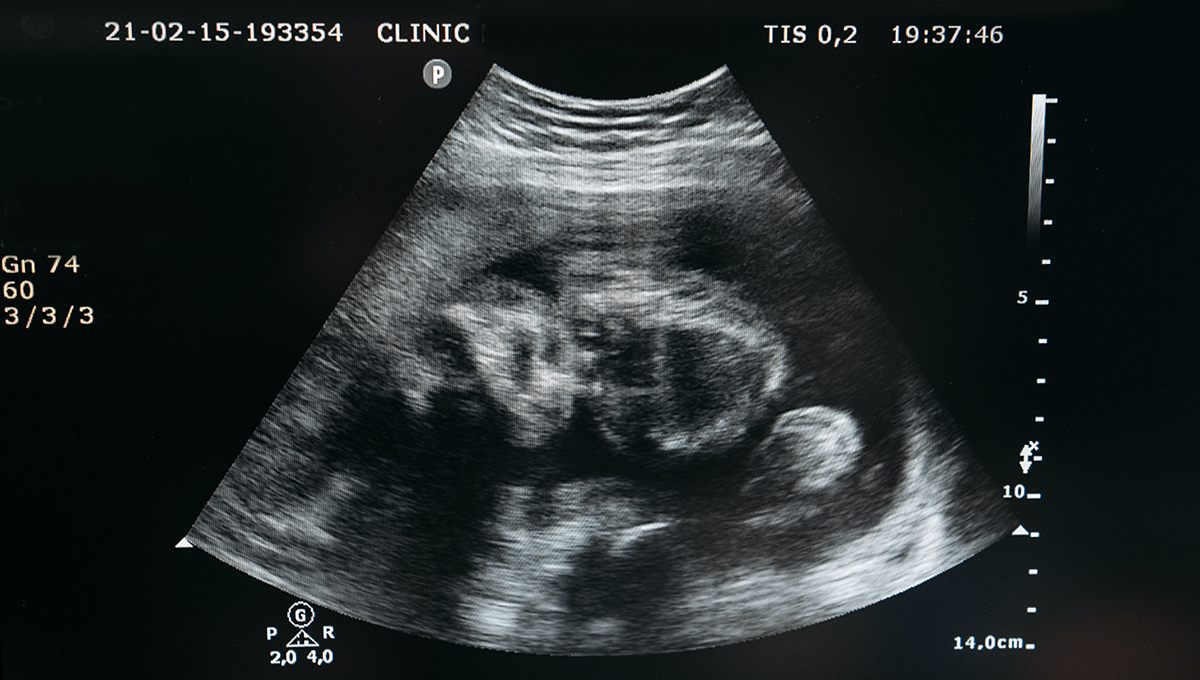

1. Tes ultrasonografi (USG)

Cara mengetahui jenis kelamin bayi yang paling umum dijalani ibu hamil adalah pemeriksaan ultrasonografi (USG).

USG termasuk tes pemeriksaan kehamilan rutin dengan menggunakan gelombang suara. Tes ini tidak khusus digunakan untuk mengetahui jenis kelamin bayi.

Lebih dari itu, pemeriksaan ini berguna memantau perkembangan dan kesehatan bayi secara keseluruhan.

Kebanyakan dokter menjadwalkan USG saat usia kehamilan memasuki 18 minggu sampai 21 minggu.

Tapi, jenis kelamin bayi bisa dilihat dengan USG saat usia kehamilan memasuki 14 minggu.

Namun, prediksi jenis kelamin bayi dengan USG tidak selalu akurat.

Pasalnya, terkadang posisi bayi tidak pas atau alat kelamin tidak jelas. Dengan begitu, simpulan yang dihasilkan bisa saja keliru.